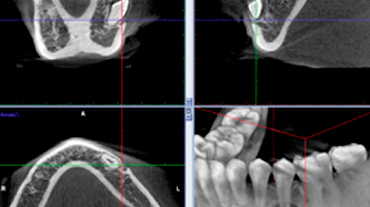

Exploración de impresiones CBCT

Modelos 3D precisos y mayores capacidades de diagnostico